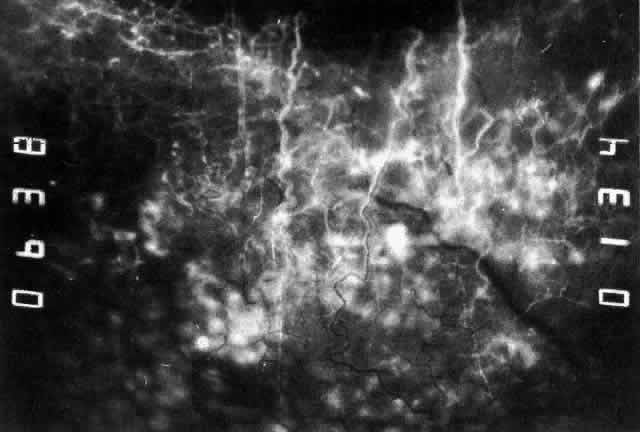

Simple and nodular episcleritis differ in their clinical courses, but in both the edema and infiltration are entirely within the episcleral tissues. The sclera is not involved. The maximum congestion is in the superficial episcleral network, with some slight congestion of the conjunctival vessels and deep episcleral vessels (Fig. 10). The intraocular structures are not involved in either variety, nor is the visual acuity affected. Anterior segment fluorescein angiography reveals a normal vascular pattern but a very rapid flow rate, with the whole transit of the dye being completed within 2 or 3 seconds (Figs. 11 and 12).

Fig. 11. Anterior segment fluorescein angiogram of a 45-year-old woman with simple episcleritis. At first transit of dye, all the vessels are dilated and filling simultaneously. However, the vascular pattern is not disturbed.

Fig. 12. Angiogram of the same 45-year-old woman in Figure 11 one second later. Within 1 second, all the vessels are filled and there is even, venular filling except in the deep episcleral plexus. This is the rapid filling pattern seen in all forms of episcleritis and in diffuse anterior scleritis.